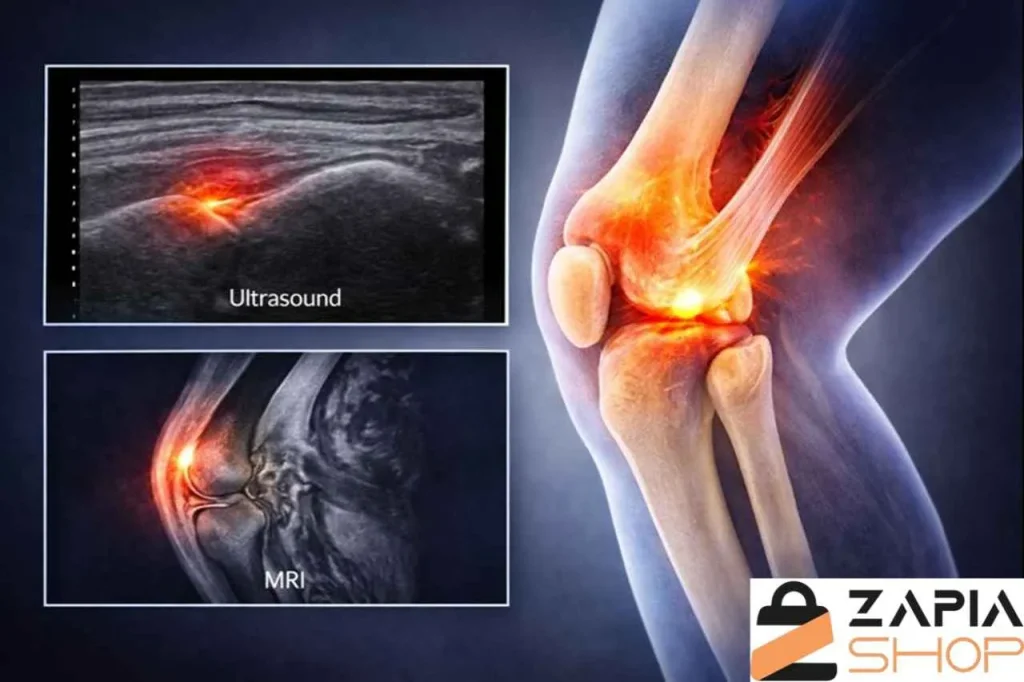

برای انتخاب بهترین روش درمان، تشخیص دقیق نوع و شدت آسیب تاندون زانو ضروری است. این فرآیند معمولاً با بررسی تاریخچه آسیب، معاینه فیزیکی و در صورت نیاز، انجام روشهای تصویربرداری پیشرفته انجام میشود.

پزشک تلاش میکند تا مشخص کند آیا آسیب به شکل کشیدگی تاندون زانو است یا پارگی کامل، و همچنین موقعیت دقیق پارگی و وضعیت پاتلا زانو را ارزیابی کند. ترکیب تستهای بالینی و تصویربرداری کمک میکند تا برنامه درمانی دقیقتری طراحی شود.

مراحل اصلی تشخیص:

- بررسی شرح حال و سوابق آسیبدیدگی یا بیماریهای مرتبط

- معاینه فیزیکی برای ارزیابی درد، تورم و توانایی حرکت پا

- انجام تستهای عملکردی مانند بالا آوردن پا در حالت صاف

- بررسی وضعیت و راستای پاتلا زانو برای تشخیص افتادگی یا جابهجایی

- استفاده از سونوگرافی برای مشاهده سریع بافت تاندون

- انجام MRI برای تعیین محل دقیق و شدت پارگی

- مقایسه علائم با آسیبهای مشابه مانند کشیدگی یا التهاب تاندون